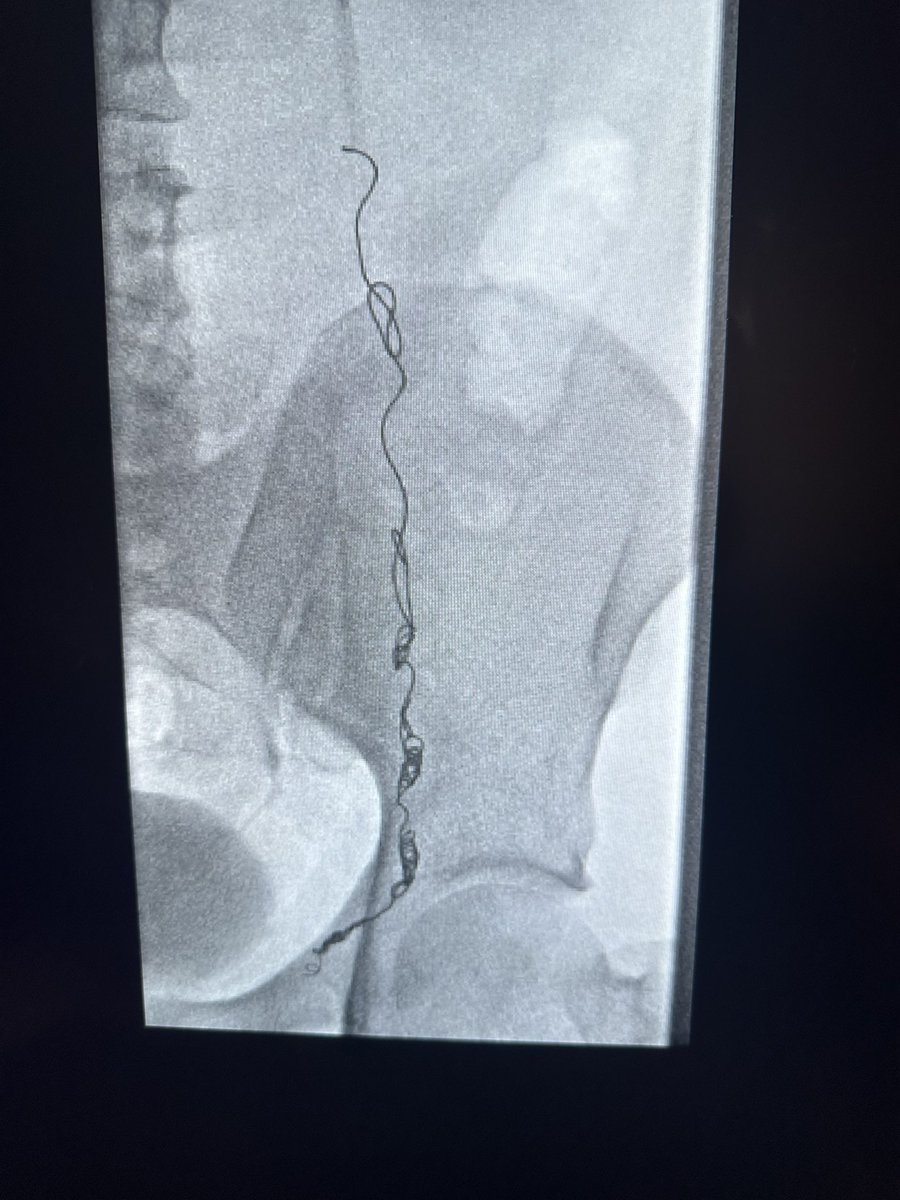

ابداع من أخصائية الأشعة @itskhulud_ في توضيح ما نراه بالأشعة التداخلية اثناء علاج دوالي الخصية العائدة بعد الجراحة حيث يتم ربط القليل من الاوردة الكبيرة وترك الباقي. احدث التقنيات والتطورات الطبية متوفرة في جامعة الملك سعود @ksumedicalcity

Naif Alsaikhan | د. نايف بن حمد الصيخان tweet mediaNaif Alsaikhan | د. نايف بن حمد الصيخان tweet media

في علاج دوالي الخصية بالقسطرة تستخدم أدوات إصمام متعددة مثل اللفائف و السدّات والصمغ الطبي و الرغوة المصلّبة منذ عشرات السنوات وهي ادوات آمنة وفعالة و لها استخدامات متعددة في اجزاء كثيرة في الجسم منها المخ والصدر والكبد والأطراف

د.سلطان رباح الحربي | Dr. Sultan R.Alharbi tweet mediaد.سلطان رباح الحربي | Dr. Sultan R.Alharbi tweet mediaد.سلطان رباح الحربي | Dr. Sultan R.Alharbi tweet media